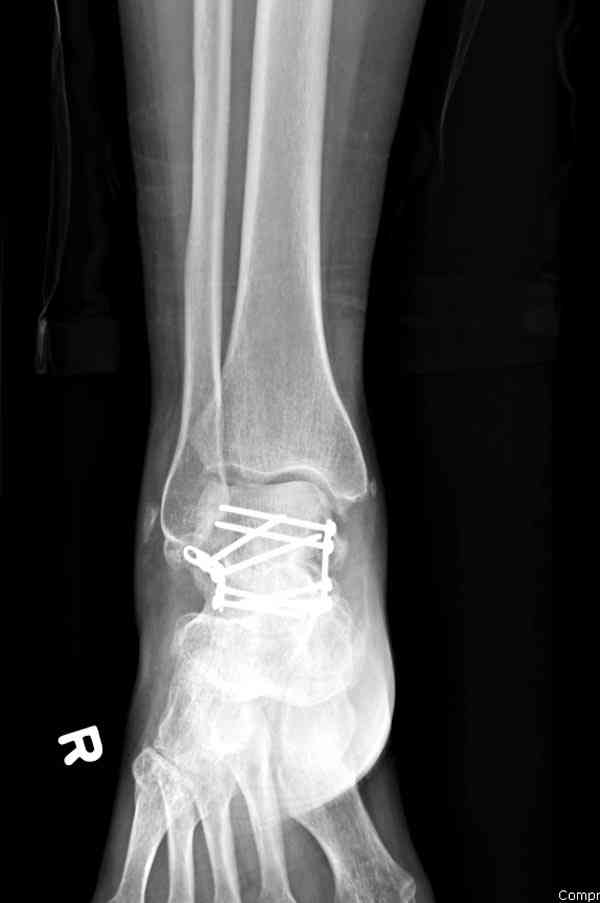

Случай с множественным оскольчатым переломом тарана оперированный из двойного доступа.

Через 2 мес.: